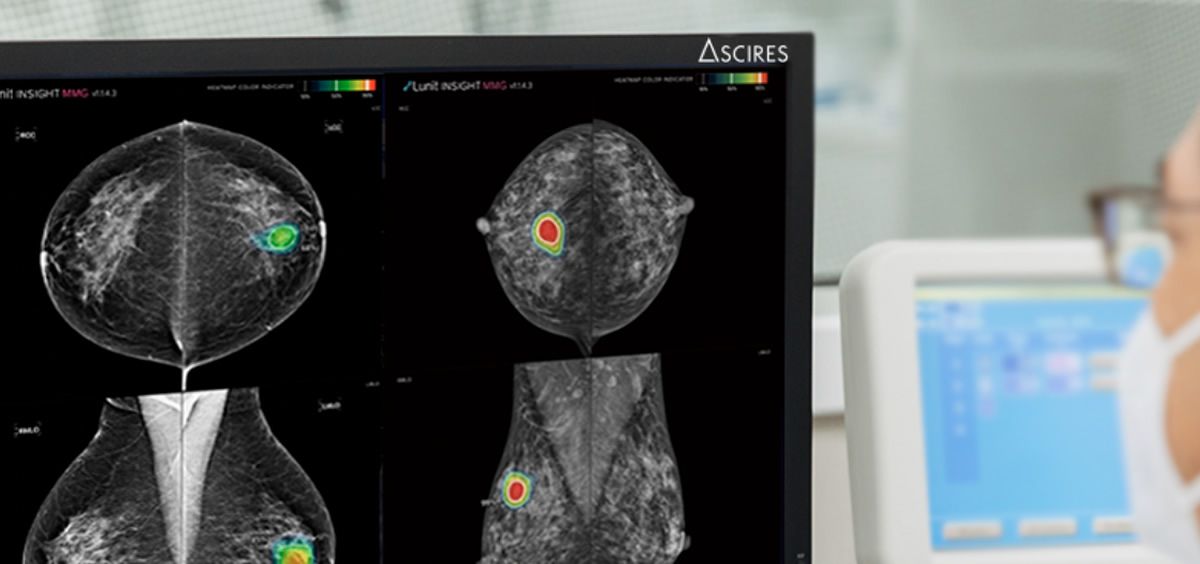

Ascires es el primer equipo español en incorporar a sus protocolos diagnósticos de mama un software de inteligencia artificial avalado por los principales certificados internacionales. Este ofrece un 96% de precisión lo que reduce significativamente las posibilidades de que se produzcan falsos negativos en las revisiones de mama mediante mamografías de rutina. Algo fundamental si tenemos en cuenta que estas e realizan de forma anual o bianual.

El experto señala que el software tiene un índice muy preciso de detección de lesiones, “hablamos de milímetros, lesiones que pueden pasar muchas veces desapercibidas para el ojo humano”, lo que contribuye a evitar los falsos negativos

El experto señala que el software tiene un índice muy preciso de detección de lesiones, “hablamos de milímetros, lesiones que pueden pasar muchas veces desapercibidas para el ojo humano”, lo que contribuye a evitar los falsos negativos.

Ascires Grupo Biomédico adquirió en 2021 este software de inteligencia artificial y actualmente es la primera empresa española en implementarlo en el día a día de su actividad clínica. El pasado mes de febrero se implantaba en la clínica con la que cuentan en Barcelona (actualmente ya está disponible en todas las demás) y, en estos meses Santabárbara asegura que se han identificado varios tumores que, sin la ayuda de este software, hubieran sido sin duda falsos negativos.

“La filosofía que tenemos es que es una herramienta de alta precisión para el radiólogo. Podemos hablar de una especie de lente para detectar lo que el ojo humano no puede percibir, para diagnosticar pequeñas lesiones en sus estadios iniciales, que es cuando realmente queremos diagnosticarlas para que no haya ningún tipo más de progresión. E incluso, para que con la propia biopsia podamos extraer la lesión entera si es posible. Para nosotros es muy revolucionario porque estamos haciendo un screening mucho más previso y maximizando las tasas de éxito”, concluye.